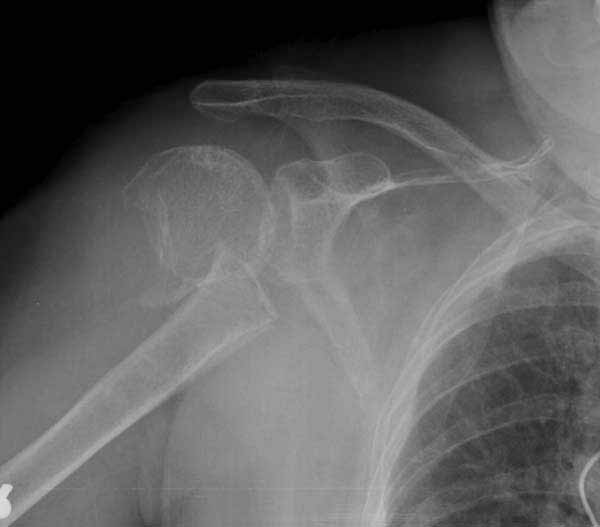

Немного причин, приводящих к вывихам после фиксации переломов проксимального плеча. В результате несоответствия суставной поверхности лопатки и головки плеча из-за потери кости по задней поверхности головки плеча или в задней половине суставной впадины. Или в результате отсутствия мягкотканого покрытия, к которому можно отнести разрывы манжетки или суставной капсулы. А также когда повреждается нерв.

Набор мелких снимков не отражает истинную картину суставной поверхности лопатки, а также качество репозиции головки плеча. Необходимо доказать аксиальным снимком наличие покрытия головки. Правильная маркировка на рентген снимках и соответствие с выставленным диагнозом гарантирует от ошибок со стороной во время операции!

Здесь результат похожего случая, больная 87 лет, отягощенная сердечными делами и два года назад установка pacemaker и нескольких стентов. На третий день, сегодня утром сделали операцию. Послеоперационный псевдовывих связанный с релаксацией мышц и общим обезболиванием.